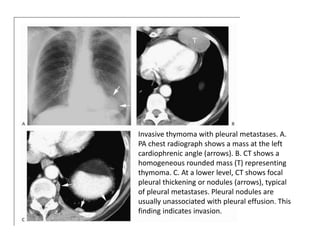

Invasive thymoma with pleural metastases. A.

PA chest radiograph shows a mass at the left

cardiophrenic angle (arrows). B. CT shows a

homogeneous rounded mass (T) representing

thymoma. C. At a lower level, CT shows focal

pleural thickening or nodules (arrows), typical

of pleural metastases. Pleural nodules are

usually unassociated with pleural effusion. This

finding indicates invasion.